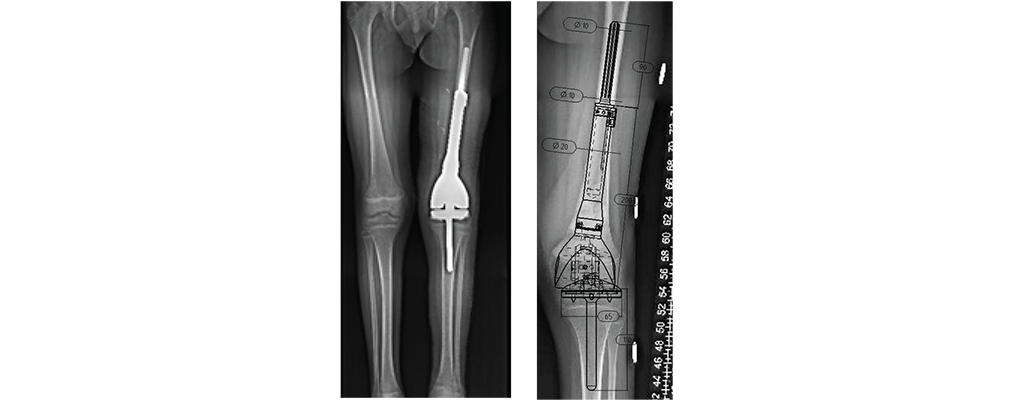

With more than 35,000 individual solutions during the last 50 years. We helped many patients regain their quality of life.